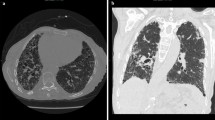

There has been a revolution in the prevailing concensus regarding the pathogenesis of IPF over the course of the past couple of decades, with a retreat from paradigms solely based on IPF as an immune-mediated disorder involving chronic inflammation of the lower airways which progresses to fibrosis, towards a view of IPF as a disease of abnormal pulmonary fibroproliferation/disorganised matrix deposition in the face of repetitive injury to an ageing alveolar epithelium that is genetically predisposed to UIP formation [1,2,3,4] (Fig. 6.1). The historical term “cryptogenic fibrosing alveolitis ” used interchangeably with IPF encapsulates the thinking decades ago when much of the available evidence pointed to a likely dominant role for chronic alveolar epithelial inflammation progressing to injury and dysregulated repair resulting in fibrosis, not least of all because alveolar inflammation appeared to precede fibrotic lesion development [5]. Initial enthusiasm for a chronic inflammatory basis for IPF also stemmed from observations of an excess of neutrophils within alveolar walls and the alveolar epithelial surfaces in IPF [6]. In addition, immune complexes of mainly IgG were found in the epithelial lining fluid of IPF individuals [7]. In an older study, alveolar inflammation was found to occur in approximately half of clinically unaffected family members who are at risk of inheriting autosomal dominant idiopathic pulmonary fibrosis, termed familial interstitial pneumonia (FIP) [8]; however a more recent larger study (FIP defined as at least two family members with IIP including IPF in at least one affected individual per family) failed to replicate this finding, with no difference seen in inflammatory cell proportions in BAL fluid among at-risk (asymptomatic first-degree relatives of FIP patients) and healthy control subjects [9]. Part of the shift away from the notion of chronic inflammation as a basis for IPF came with the tighter concensus surrounding the pathologic classification of the disease two decades ago, which up to then had included what are now widely accepted as being separate forms of idiopathic interstitial pneumonia such as non-specific interstitial pneumonia and acute interstitial pneumonia, for which anti-inflammatory treatments may show more benefit [10,11,12]. A sentinel event in shaping the current prevailing view that immunomodulatory therapies are to be avoided in IPF came with the discovery in the PANTHER study that a then standard-of-care though unproven therapy for IPF, the combination of oral corticosteroid, azathioprine and N-acetylcysteine was not only inefficacious in IPF but led to higher mortality and hospitalisation within a mean of only 32 weeks of treatment versus placebo [13]. The dawn of a new era of therapeutic options for what was until then an untreatable disease arrived on May 18, 2014, with the simultaneous publication of phase III studies of two very different disease modification compounds, pirfenidone and nintedanib, which both share antifibrotic properties and have highly pleiotropic mechanisms of action, suggestive of a need in IPF to address multiple redundant wound-healing pathways in order to control what is a complex polygenic disorder [14, 15]. Nearly all of the compounds currently in development for the treatment of IPF involve mechanisms relating to lung tissue repair, regeneration, inhibition of epithelial cell apoptosis and inhibition of collagen deposition, with little interest in an anti-inflammatory/immunosuppressing approach [2], given the unequivocal failures of such approaches in the past [13, 16]. Within these few years, long-held theories of IPF pathogenesis had been overturned.

A proposed pathogenetic model of idiopathic pulmonary fibrosis. (From Ref. [4])

The delight that universally accompanied the long-awaited emergence of IPF medications with some disease-modifying effects needs to be tempered against the ongoing unmet needs of these patients, who are far from cured by current antifibrotic strategies. Somewhat at odds with a more dismissive view of an immunologic and inflammatory role in IPF pathogenesis are a wealth of data that provides the smoking gun to an immunobiological role in either the initiation or progression of IPF, which remains incompletely understood and, arguably therefore, unsuccessfully addressed in treatment approaches. Such a role may be more important for subtypes of IPF that await elucidation, though it is also plausible that the association of immunologic abnormalities with IPF are a process that is downstream from fibrosis-driven biology [2, 17]. Strongly pointing towards a chronic immune process in IPF are the replicated observations in IPF lung tissue of lymphoid aggregates, suggestive of lymphoid neogenesis [17,18,19,20]. These are found in close proximity to fibroblastic foci and are composed of mainly activated CD3+ T lymphocytes and mature dendritic cells, with a subset of activated CD20+ cells, with some evidence also pointing to chemokine receptor (CCR)6 expression in these infiltrates, as found on memory T cells, Th-17 cells, B cells and dendritic cells [18, 20] (Fig. 6.2). These aggregates were seen in increasing numbers in IPF explants versus less advanced IPF lung surgical biopsy specimens, suggestive of a sustained role for such lymphoid tissue in progressive IPF [19]. The picture is confused however by the observation that these tertiary lymphoid structures (TLS) contain non-proliferating and non-apoptotic mature CD45RO+ T and B cells [18, 19], which has led to a hypothesis of these cells homing to the lung from the systemic circulation, although data is lacking to support such an origin [19].

Idiopathic pulmonary fibrosis inflammatory infiltrates. All photomicrographs show the tissue stained with Fast Red and haematoxylin counterstain. (a–f) The photos have a magnification of ×200. (g, h) The photos have a magnification of ×400. (From Ref. [20])

Another difficulty in dismissing an important role for the immune system in IPF lies in the repeated observation of areas of histopathologic UIP and non-specific interstitial pneumonia (NSIP) in the same patient when biopsies are obtained from different lobar locations, a phenomenon thought to occur in 13–26% of cases [21, 22]. NSIP can have varying degrees of alveolar wall inflammation by predominantly lymphocytes and plasma cells in addition to fibrosis and has a better prognosis than UIP, but individuals with discordant UIP and NSIP on their multiple biopsies have a poor prognosis similar to those with concordant UIP on multiple biopsies [21, 22]. In support of an endotypic difference among the two diseases, NSIP fibroblasts appear to behave more like normal fibroblasts than is seen in IPF fibroblasts, where the latter exhibit greater contractility and secrete greater amounts of fibronectin and TGF-β1 [23]. There is a great need to further improve our understanding of the potential for an evolution of NSIP into fibrotic NSIP and later into UIP, as immunomodulatory therapy for NSIP, a putative early treatment strategy for IPF, demonstrates some efficacy versus being ineffective in UIP [24]. Some have suggested that a greater understanding of rheumatoid arthritis-associated interstitial lung disease, where the undoubtedly inflammatory disease of rheumatoid arthritis can result in either an NSIP or UIP pattern, offers a good model for gaining further insight into the pathogenesis of both of these related interstitial pneumonias [25]. Lending support of such a model, a recent study that established and validated a role for a biomarker index of three plasma molecules, MMP-7, surfactant protein D and osteopontin in discriminating IPF from alternative interstitial lung diseases (adjusted area under the curve of 0.766, excluding RA-ILD), could not distinguish IPF from RA-ILD [26]. Of interest in such an IPF model is the shared risk factor of chronic tobacco smoke exposure in both idiopathic and RA-associated UIP. In recent times, the contributory role of immune mediators and inflammatory cells have once again gained more acceptance in schemata of IPF pathogenesis, though far more questions than answers are found [27]. The remainder of this chapter will discuss the evidence that implicates a variety of inflammatory and immunologic processes in contributing to the pathogenesis of IPF.

There is increasing awareness of roles for adaptive immunity in IPF, potentially in initiation and/or disease progression. As mentioned earlier, lymphoid aggregates are a recognised pathologic feature of IPF lesions and in most if not all other disease settings are usually pathognomic for the presence of chronic immune responses [18, 19, 108]. From an immunity standpoint, there is a predominance of T cells in BAL fluid and lung tissue from IPF patient, with CD3+ T lymphocytes and mature dendritic cells found in the vicinity of fibroblastic foci and regions of high collagen deposition [17,18,19, 68]. The aggregates also display CD20+ B lymphocytes, which form cohesive clusters in the centre of these aggregates (Fig. 6.7). In contrast with COPD or idiopathic pulmonary arterial hypertension, these tertiary lymphoid structures have non-proliferating and non-apoptotic features and therefore are likely to have already been activated when recruited to the lymphoid aggregate lesions [18]. The tertiary lymphoid structures include mature dendritic cells, and because it is known that activated T cells within the lung retain competency in effector cytokine production, it is plausible that chronic pulmonary inflammation could result from reactivation of memory T cells by maturing dendritic cells within IPF lymphoid aggregates [18, 109, 110].

Accumulation of CD20+ B-cell aggregates in the lung tissue of IPF patients around areas of pulmonary fibrosis that are normally absent in healthy lungs. (a) Masson’s trichrome stain of the lung tissue of an IPF patient. (b) Immunohistochemical stain of CD20+ B cells in a serial section of the same tissue. The CD20+ aggregates accumulate in areas where there is fibrosis (blue areas in a). (From Ref. [110])

In a study of 53 IPF patients’ surgical lung biopsies, multivariate analyses showed that increasing fibroblastic foci scores were independently associated with greater declines in FVC and DLCO at 6 and 12 months of follow-up, but unexpectedly at the time of this study, increasing interstitial mononuclear cell infiltrates were also independently associated with lung function decline, though only at 6 months, leading the authors to postulate that such active inflammation could have a role early in the development of fibrosis, or represent an epiphenomenon related to fibroblastic activity [111].